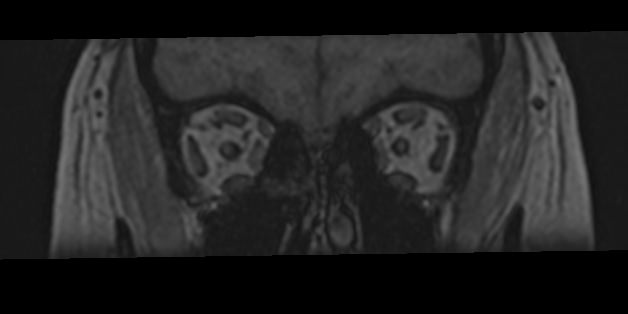

МРТ глазных орбит является современным способом диагностики патологии глазниц, в которых расположены глазные яблоки и их придатки (окружающая жировая клетчатка, зрительные нервы, слезные железы, мышцы глаза, связочный аппарат, кровеносные сосуды). МРТ орбит также позволяет получить детальную информацию о состоянии мягких тканей периорбитальных областей (тканей, окружающих глазницу).

Магнитно-резонансную томографию назначают при необходимости детального изучения мягкотканных структур глазниц. В результате исследования получают срезы анатомической области, на которых можно рассмотреть мельчайшие элементы. МРТ орбит обеспечивает визуализацию следующих структур:

• элементы глазного яблока, включая оболочки;

• периорбитальная клетчатка;

• мышечный аппарат;

• зрительный нерв;

• слезные железы.

Ангиорежим позволяет изучить сосуды глаза (глазная артерия и вены сетчатки).

• эндокринная офтальмопатия;